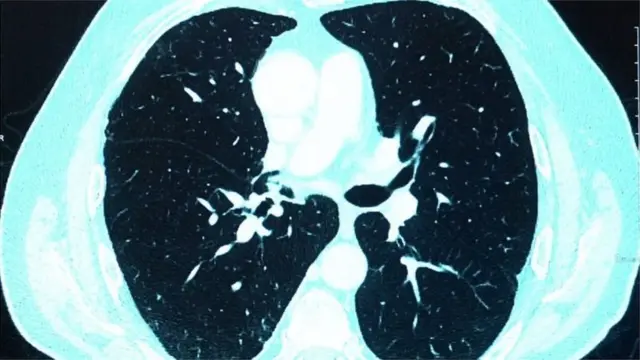

দেখা গেল, তাদের ফুসফুসের গুরুতর ক্ষতি হয়ে গেছে, অবসন্নতা ও বুক ধড়ফড়ানি দেখা দিচ্ছে, স্মৃতিশক্তি কমে গেছে, অনেকে এতটাই দুর্বল হয়ে পড়েছেন যে হাঁটাচলা পর্যন্ত করতে পারছেন না - স্বাভাবিক অবস্থায় ফেরত আসতে তাদের মাসের পর মাস সময় লাগছে, কাউকে কাউকে ফিজিওথেরাপি নিতে হচ্ছে।

"রোগীরা বলে, তারা মানসিক অবসাদে ভুগছেন, তাদের কিছু ভাল লাগছে না, কিছু করতে ইচ্ছা করছে না। কারও কারও হঠাৎ করে মনে হয়, শ্বাস বন্ধ হয়ে যাচ্ছে বা দম বন্ধ হয়ে যাচ্ছে। কারও কারও ফুসফুসে জটিলতা দেখা দেয়।"